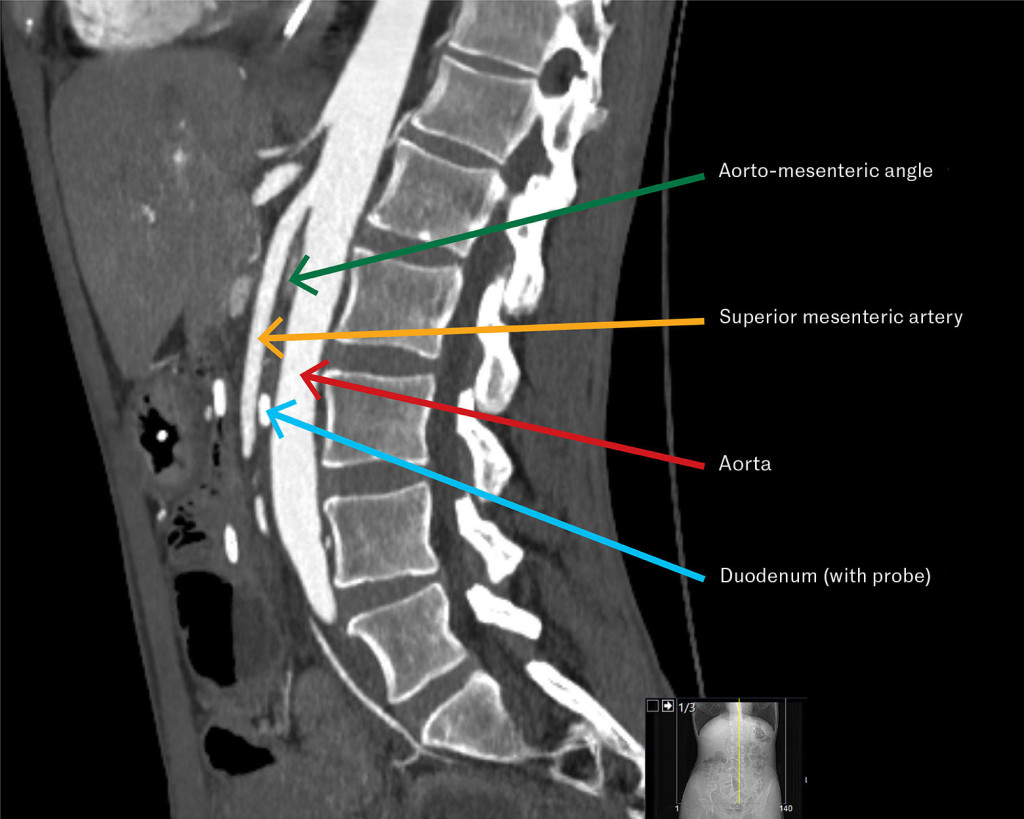

Narrow angle between superior mesenteric artery and aorta

The CT image shows a sagittal section of the abdomen revealing a narrow angle between the superior mesenteric artery and abdominal aorta, which, along with symptoms and endoscopic findings, led to the diagnosis of superior mesenteric artery syndrome.

Based on the patient's symptoms and the gastroscopic finding of gastric retention, superior mesenteric artery syndrome was suspected (see illustration). CT angiography of the abdominal vessels showed an angle between the aorta and the origin of the superior mesenteric artery of 18 degrees (normal is > 25 degrees), and the aortomesenteric distance at the level of the duodenum was 5 mm (normal is > 10 mm). The findings were consistent with the diagnosis (1).

The distal duodenum is situated between the aorta and the superior mesenteric artery. If the angle between the aorta and the superior mesenteric artery becomes too acute, it can lead to compression of the distal duodenum. This in turn can lead to gastric retention, resulting in symptoms from the upper part of the stomach, such as pain, bloating and vomiting. Emaciation with loss of adipose tissue in the aortomesenteric space is the most common cause. The primary treatment is intensive nutritional therapy, with the goal of rebuilding the 'fat pad' to increase the angle and facilitate passage through the duodenum. Surgery is recommended if therapy fails (1).